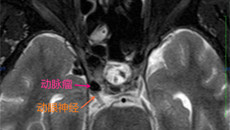

Normal 0 7.8 磅 0 2 false false false MicrosoftInternetExplorer4 失明,又称为盲,指视力残疾中程度较重的一类。盲证最早见于《素问·生气通天论》, 指目茫茫无所见;《难经·二十难》记载:“脱阴者,目盲。”现代医学则认为该病病因及病变部位较多,有先天与后天之分。后天的病因中颅内动脉瘤是其...09.162015